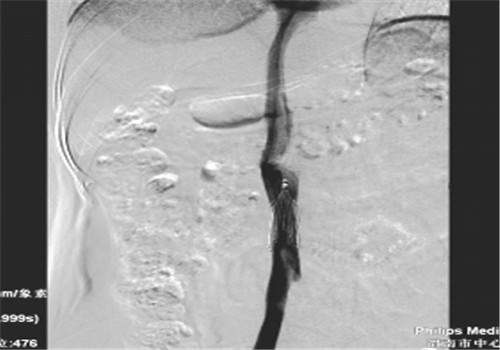

8月中旬患者来院复查,顺利骨取出科钢板,右下肢未见深静脉血栓,于8月14日行下腔静脉滤器取出术,手术顺利,历时30分钟。